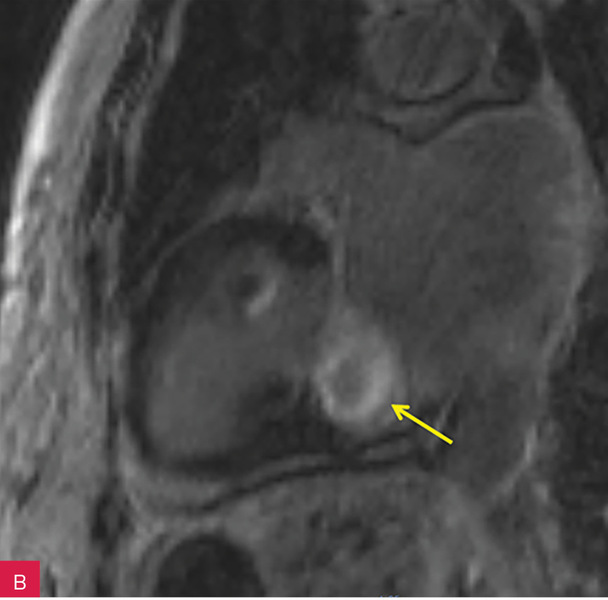

Rycina 7A-D. Obrazy rezonansu magnetycznego w osi krótkiej na wysokości pierścienia mitralnego: czarnej krwi T1-zależne TSE (A); czarnej krwi T2-zależne HASTE (B); T1-zależne echa gradientowego dynamicznie podczas podawania środka kontrastowego (C); sekwencja SSFP, pojedynczy obraz w osi krótkiej (D). W dolno-bocznej części pierścienia mitralnego od strony światła lewej komory zmiana (strzałki) niskosygnałowa we wszystkich ważeniach sygnału

W celu weryfikacji zmiany i oceny charakterystyki tkanki wykonano CMR,

w którym stwierdzono w dolno-bocznej części pierścienia mitralnego od strony światła lewej komory zmianę odpowiadającą morfologicznie CCMA, obejmującą 7,3 cm obwodu pierścienia mitralnego, o grubości w osi krótkiej do 25 mm, w osi długiej do 21 mm; zmiana ulegała brzeżnemu wzmocnieniu kontrastowemu i powodowała ograniczenie ruchomości tylnego płatka zastawki mitralnej, obejmowała struny ścięgniste mięśnia brodawkowatego tylno-przyśrodkowego. Ponadto uwidoczniono znacznie powiększone przedsionki z istotnym włóknieniem – jak w restrykcji (ryc. 7, 8).